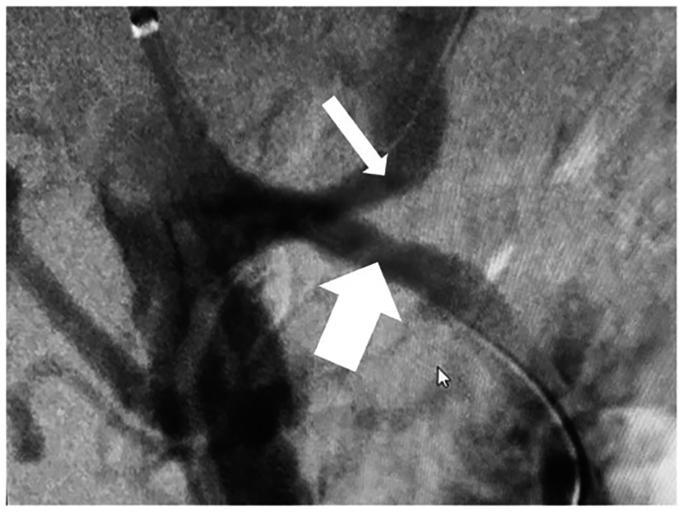

The celiacomesenteric trunk (CMT) is a rare anatomical variant where the celiac axis and superior mesenteric artery share a common origin. Despite its rarity, CMT has significant implications across various medical fields, particularly in surgical planning and interventional procedures. We report a case of chronic mesenteric ischemia owing to atherosclerotic stenosis at the CMT bifurcation, necessitating a complex interventional approach. Kissing covered stent angioplasty was successfully performed, resulting in revascularization, symptom resolution, and no restenosis at 1-year follow-up. This report highlights the feasibility and effectiveness of the kissing stent technique in managing complex CMT bifurcation obstructions in patients with chronic mesenteric ischemia.

腹腔肠系膜干(CMT)是一种罕见的解剖变异,即腹腔干和肠系膜上动脉有共同的起源。尽管CMT罕见,但它在各个医学领域都有重要意义,尤其是在手术规划和介入操作方面。我们报告一例因CMT分叉处动脉粥样硬化狭窄导致的慢性肠系膜缺血病例,需要采用复杂的介入方法。成功实施了吻合法覆膜支架血管成形术,实现了血管再通、症状缓解,且在1年随访时无再狭窄。本报告强调了吻合法支架技术在处理慢性肠系膜缺血患者复杂CMT分叉处梗阻方面的可行性和有效性。